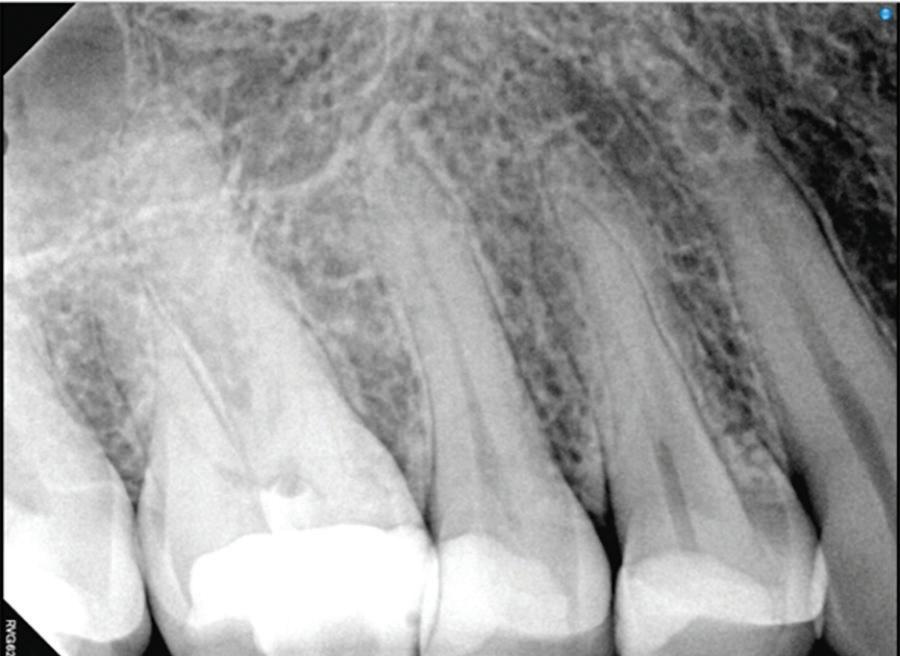

Implications of a persistent CAIPP defect

A CAIPP defect can be expected to accompany the radicular crack or eventually develop. These bony dehiscences are not easily accessible and are not predictably amenable to current periodontal therapies because bacteria reside within the crack and not on the root surface. These defects are often missed by traditional radiography and probing due to their narrow width and interproximal location.

These CAIPP lesions are best identified and monitored with high-resolution CBCT scans (Fig 5). However, even advanced CBCT systems, with voxel sizes as small as 0.075 mm, are not capable of reliably detecting cracks, which are typically much narrower.45 Therefore, the presence of a CAIPP defect, combined with careful clinical diagnostics and evaluation, remains the most reliable indirect indicator of a crack with radicular extension.

The presumed clinical significance of a lingering CAIPP defect is that the persistent biofilm in the crack can lead to further periodontal breakdown and symptoms. However, the changes in these areas were monitored over the course of

previous studies, and these bony lesions did not progress over time and remained asymptomatic.4,26 Together, these studies demonstrated that the persistent bony defect adjacent to the cracks may remain stable and asymptomatic over time, making saving teeth with this technique a realistic option for patients.

Fig 5. CBCT images of a crack-associated isolated periodontal pocketing defect associated with a distal crack in the mandibular right first molar. A. Sagittal view showing angular crestal bone loss (arrow) along a distal radicular crack at the cervical margin. B. CBCT 3-dimensional rendering showing the defect (arrow) at the distal root. C. Axial view showing the defect (arrow) at the distal root.